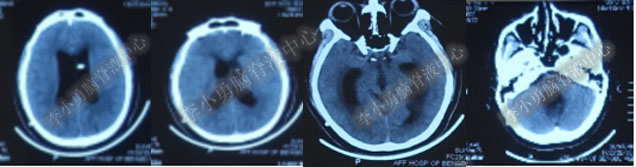

2016年5月9日因“间断性眩晕半月,恶心呕吐一周”以“梗阻性”脑积水,第1次住入北京某企业三级医院神经外科内镜组。2016年5月10日(入院后第2天)行头部MRI(图-1)检查示脑室系统扩张。

图-1:2016年5月10日头部MR

术后7天(2016年5月18日),症状有所缓解,复查头部MRI(图-2)幕上脑室较术前缩小,但是“四脑室仍扩张”,医生认为 “正常”于术后8天(2016年5月19日)出院。

图-2:2016年5月18日头部MRI